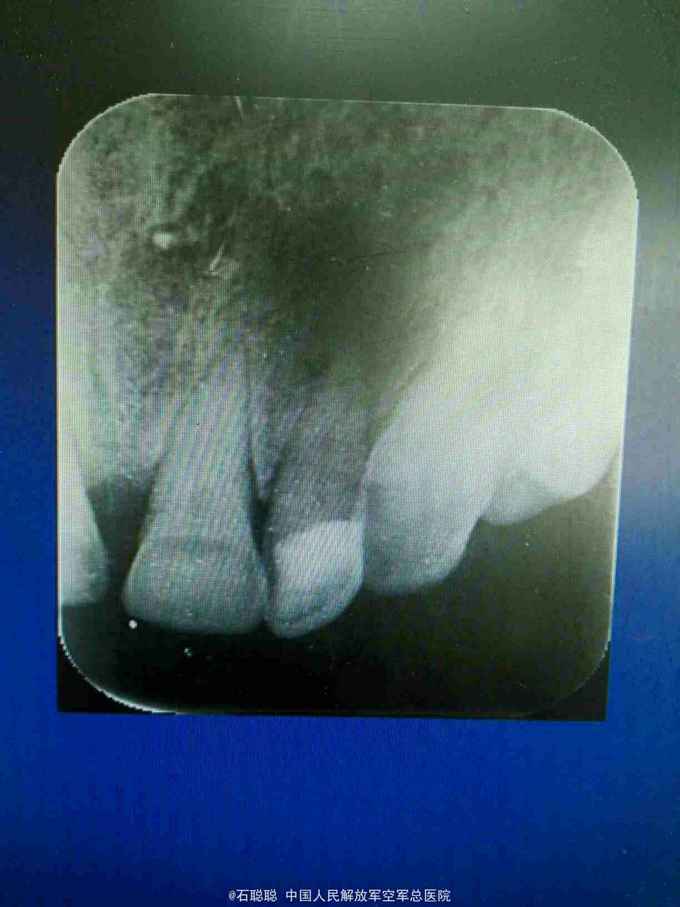

检查:左上234唇侧牙龈红肿,轻压见左上23治疗窦道口溢脓,肿胀区扪诊疼痛,左上2根尖区疼痛最为明显,左上2松动1-2度,叩痛++,唇侧树脂充填 根尖片:左上2根尖区见类圆形直径约1cm的低密度透射影,边界模糊

诊断:左上2根尖周脓肿 治疗计划:开髓引流,消炎镇痛,后期根管治疗 处置:左上2去旧充填物,见树脂充填物进去髓腔,探及根管口,疏通,见大量脓性,血性液体渗出,开放,口服头孢、甲硝唑 次日复诊: 诉肿胀疼痛减轻 查:左上234唇侧牙龈肿胀减轻,扪诊疼痛减轻,左上2松动度减轻 处:进一步疏通扩大至25#,见混浊血性渗出,继续开放 次日复诊:左上234唇侧牙龈肿胀消退,叩痛消失,松动度明显减小,冲洗,干燥,封CP棉球,告知患者一周后复诊,继续完成治疗

讨论:由于患者1年前接受了不恰当的充填治疗,导致左上2的根尖病变,引起完整病变的急性发作,引起相应部位牙龈肿胀,鼻翼旁的疼痛,治疗原则是开髓、充分引流,全身抗炎治疗,由于没有形成有明显波动感的脓肿,不建议切开引流,配合口服抗生素,炎症消退较快,继续完成后续根管治疗即可,可以在根管预备完成后,封Vitapex一个月,促进根尖区病变愈合,再完成永久充填。